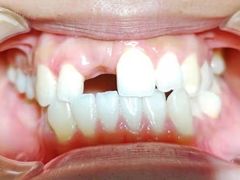

• 联合口腔(西环诊所)

• -联合口腔(西环诊所)

Enemies_6983 | 21-05-09

报错